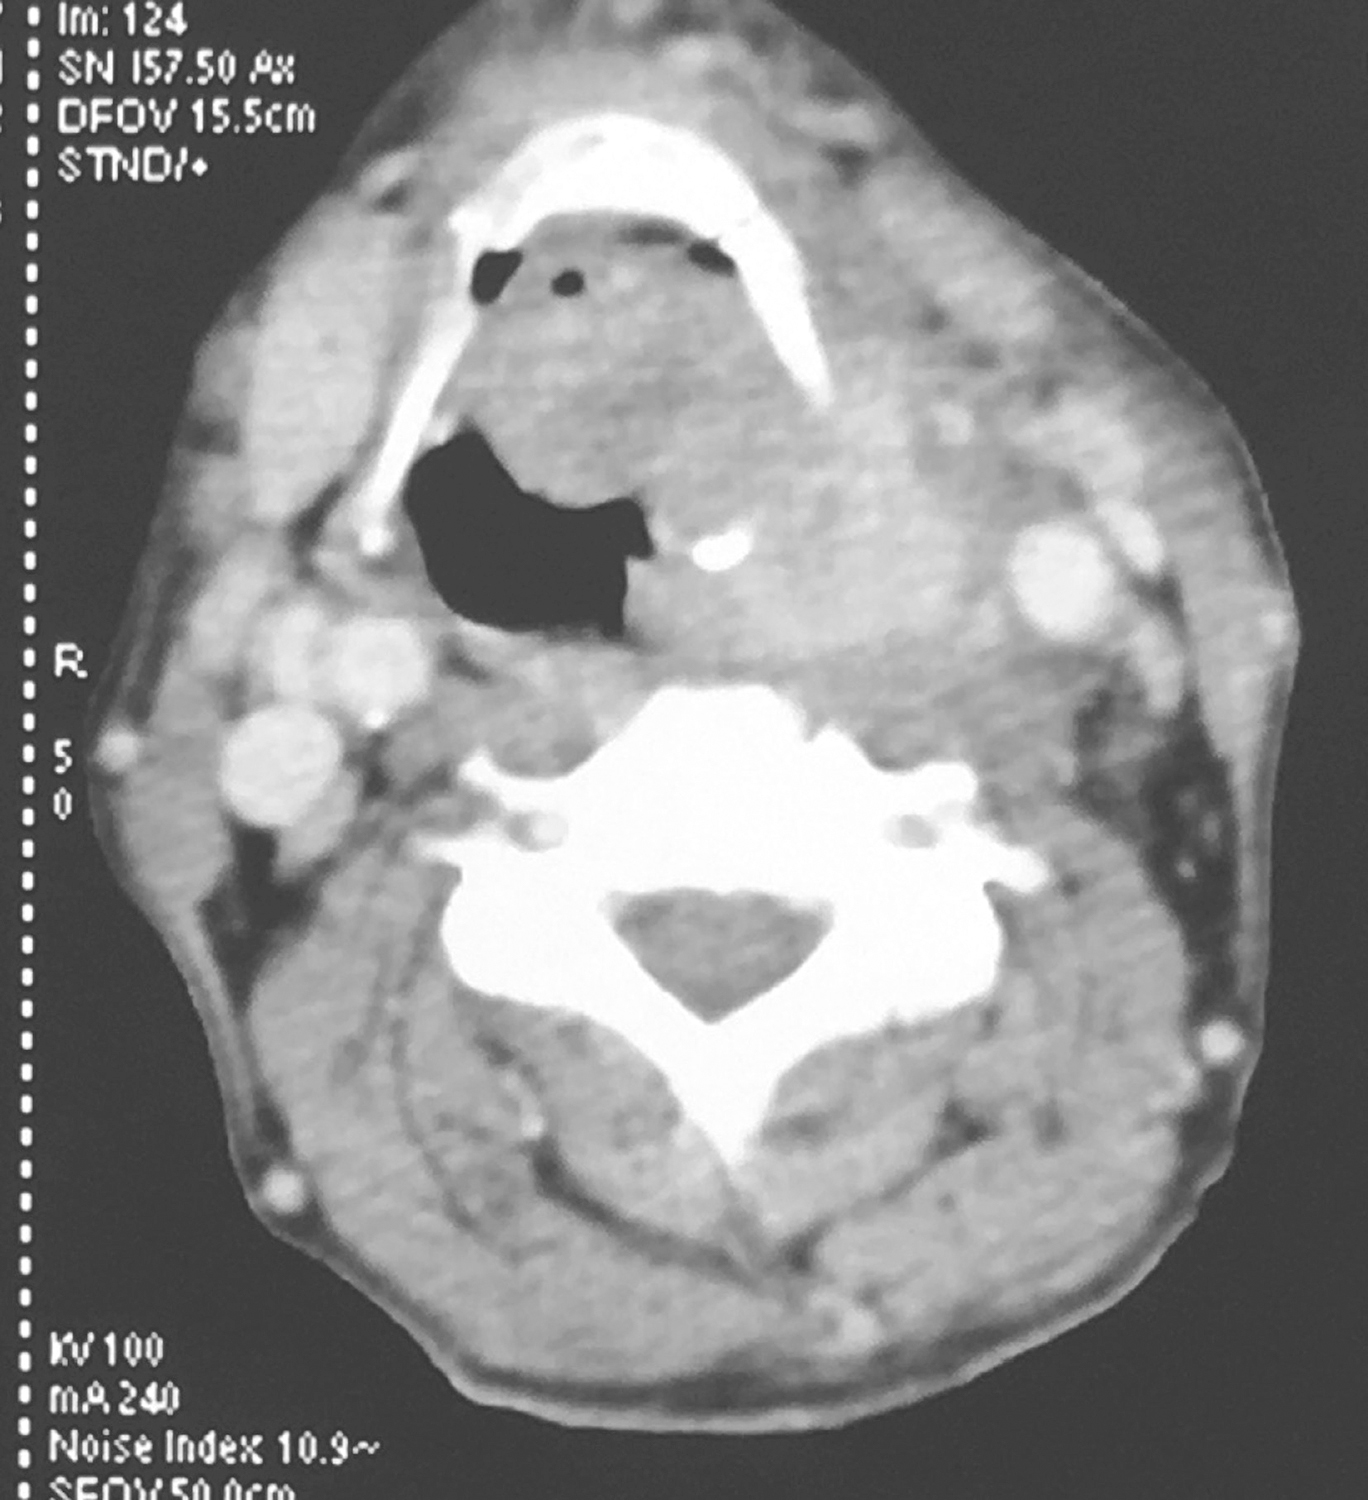

3.颈胸强化CT检查

①下咽部左梨状窝区可见软组织密度影,增强扫描可强化,向内累及左侧半喉,侵犯会厌前间隙、声门旁间隙,肿瘤侵透甲状软骨板、舌骨、累及咽侧壁及下咽后壁(图1、图2),向下累及环后区及颈段食管,向外侵犯喉外肌肉及颈前软组织。颈动脉鞘周围多枚肿大淋巴结,部分融合,边界不清,与咽喉肿瘤及颈前肌肉融合,右侧甲状腺受侵(图3),颈内静脉闭塞(图4),颈总动脉与肿瘤边界不清。右侧颈鞘周围也可见多枚肿大淋巴结,增强扫描可见强化。②双肺纹理增粗,双肺野及纵隔内未见异常。

影像学诊断:符合下咽部恶性肿瘤累及喉,双颈部多发淋巴结转移表现。

图4颈胸部增强CT示颈内静脉闭塞